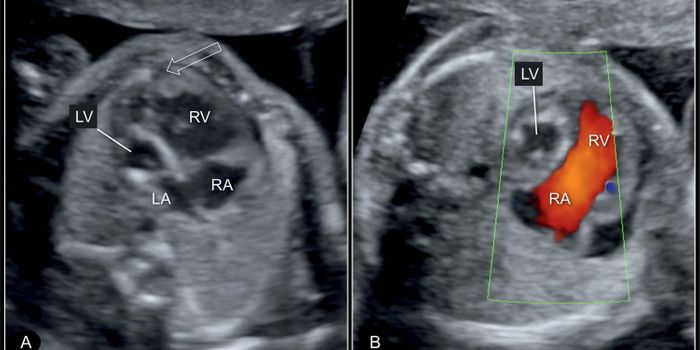

JAN 12, 2017CardiologyAn ultrasound done around 18-20 weeks of pregnancy can usually tell an expecting mother a key question she will having d ...